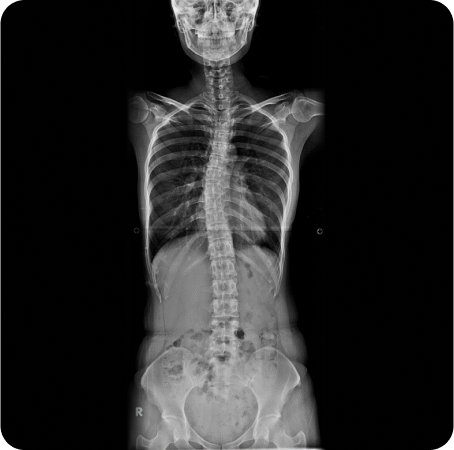

전신체형분석 X-선 검사

풀스파인 촬영으로

신체의 전체적인 문제를 파악하고

통증의 정확한 원인을 찾아

재발을 예방하고, 통증을 개선하는

치료를 합니다.

족압 검사

동적 검사

다리 길이 검사

머리부터 발끝까지 완벽하게 체형을 분석 후 통증을 만들어낸 가해자가 누군지를 찾아내서 치료합니다.